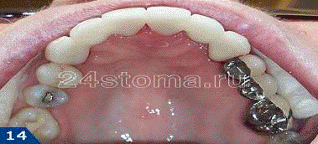

Шинирование металлокерамическими

конструкциями.

Данный вид шинирования позволяет

уменьшить подвижность зубов во всех плоскостях (фронтальной и сагиттальной).

Такие шины отвечают эстетическим требованиям пациента.

зуб

патологический шинирование пародонт

Недостатки металлокерамических шин:

. Необходимость

препарирования большого объема твердых тканей зубов.

. Эндодонтическое лечение по

показаниям.

. Изготовление шины в

несколько посещений.

. Высокая стоимость.